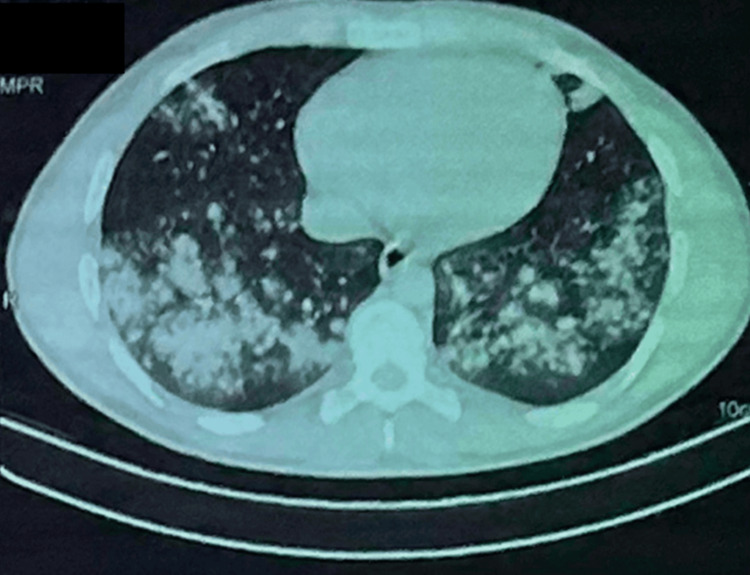

The hemogram showed hyperleukocytosis of 25020/mm3, neutrophils of 19960/ mm3 and lymphocytes of 3060/mm3. Sputum microscopy and sputum Xpert gene were negative. Bronchoscopy appearance was unremarkable, desaturation on suction maneuvers. The search for an acid-alcohol- resistant bacillus in the bronchial aspirates was negative, quantiferon was doubtful, Pneumocystis jirovecii on induced sputum was negative. Pneumococcal antigenuria was positive. Testing for common respiratory viruses, including influenza and respiratory syncytial virus, was also negative. Arterial blood gas analysis indicated respiratory acidosis with hypoxemia. High-resolution computed tomography (HRCT) of the chest demonstrated ground-glass opacities and consolidations involving multiple lung lobes (Figure 2).